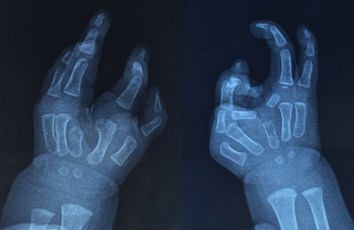

患儿出生时就发现双手为罕见的复杂先天畸形,多方求医无果的患儿家长,从当地医院医生获知,潘勇卫教授是著名的手外科专家,在治疗小儿先天畸形方面有丰富的经验,第一时间与潘勇卫主任取得联系。就诊后潘医生发现,患儿双手中指缺失,手掌呈分裂状,如同“鸟爪”一般,外观十分难看。更加严重的是,食指在功能上不但不起作用,反而妨碍其他手指的使用;而右手畸形更加复杂,手掌不但分裂,中指近节和中节指骨横七竖八藏在手掌内,只有末节从食指中段“长出”,而异位生长于食指上的中指末节,又造成食指的歪斜和旋转畸形。医学上称之为复杂的先天分裂手畸形。孩子的双手出现这样的畸形,不仅会影响其日后的生活质量,也会给他的成长留下沉重的阴影,综合考虑后,潘勇卫医师决定进行这例复杂先天性分裂手畸形矫正手术。

(术前手畸形及X线检查所见)